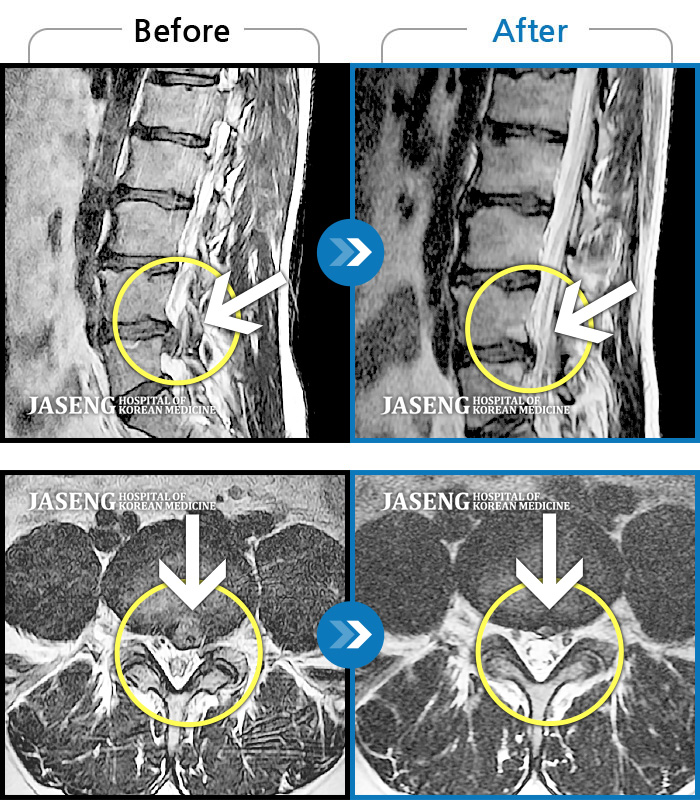

처음엔 이곳저곳 아파서 확실하게 어디가 아팠는지 몰랐는데 사고 후 일주일쯤 될 무렵 MRI촬영후 정확하게 진단을 받았습니다

허리디스크 2단계(초기) 진단을 받긴 했으나 다행히 근육량이 많아 모르고 살았는데 사고로 인해 디스크에 상처가 생겨 힘든 나날을 보내고 있습니다

디스크수술만 두번했어요 사고때문에 생긴 통증때문에 걱정이 많았어요 엄원장님 설명도 알기쉽게 해주시고 환자에대한 배려가 참 많은 분이셔서 많은 도움을 받고있습니다 적절한 치료처방으로 상태도 많이 호전되어 더 신뢰가가고 너무 감사해요 이렇게남아 감사의 글을 드립니다